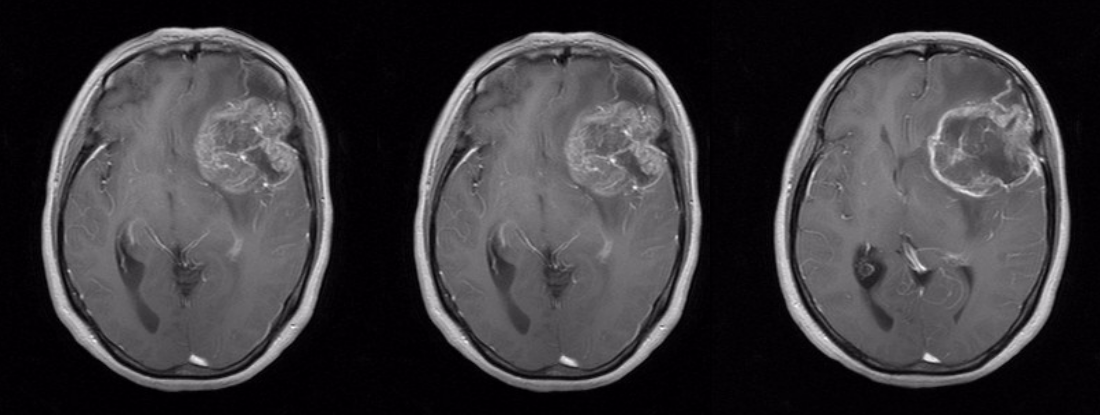

术前头颅MRI平扫加增强